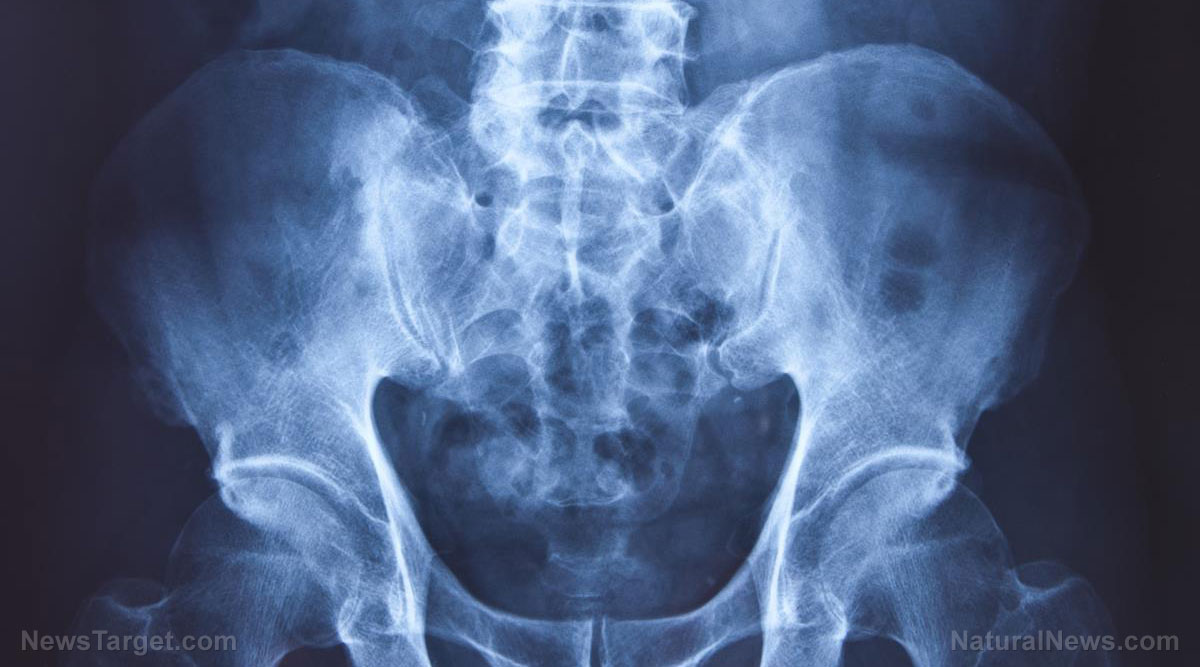

The Medicines and Healthcare products Regulatory Agency announced last month that patients would be called in for x-rays and blood tests to check for adverse reactions.

Dr Neil McGuire, clinical director of medical devices at the MHRA, said he wanted to establish whether cobalt leached from the implants was causing adverse effects.